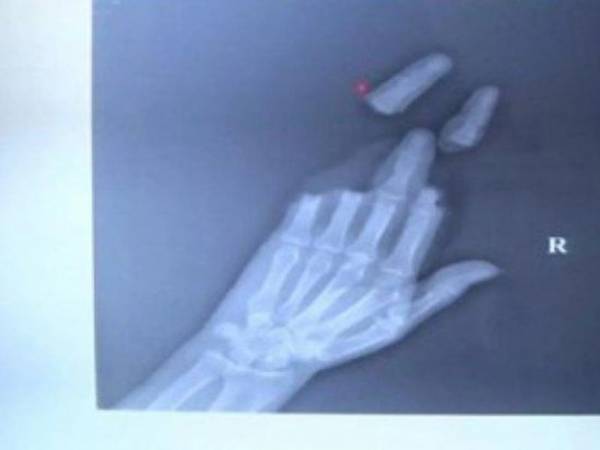

Ảnh chụp X-quang cho thấy ba ngón tay của một người đàn ông ở Giang Tô bị đứt rời sau khi thả diều trong gió lớn. Ảnh: SCMP.

Khi thả diều gặp gió lớn, người đàn ông ở miền Đông Trung Quốc đã bị dây diều cắt đứt 3 ngón tay. Sau hơn 16 giờ phẫu thuật, các bác sĩ ở bệnh viện chỉnh hình Nam Thông đã nối lại ba ngón tay cho người đàn ông đầu tiên và khâu lòng bàn tay cho người còn lại.

Một người bị dây diều cắt lìa ba ngón tay, người còn lại thì lòng bàn tay bị cắt làm hai. Hai người đã cố kéo diều trở lại khi thấy trời chuyển giông. Cùng lúc đó, một cơn gió mạnh thổi tới, quấn dây diều quanh tay của họ.

Sau hơn 16 giờ phẫu thuật, các bác sĩ ở bệnh viện chỉnh hình Nam Thông đã nối lại ba ngón tay cho người đàn ông đầu tiên và khâu lòng bàn tay cho người còn lại.